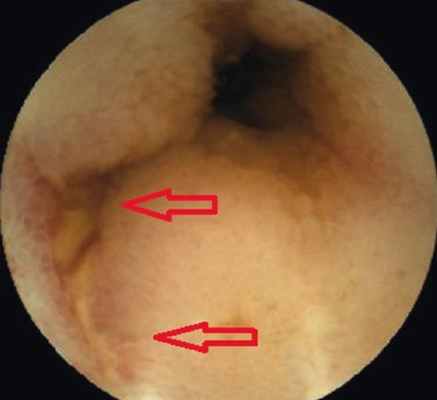

Пациентка В . , 19 лет, с подтвержденным диагнозом «болезнь Крона (язвенно-геморрагический энтерит)» с 2012 г. неоднократно находилась на обследовании и лечении в отделении воспалительных заболеваний кишечника Московского клинического научно-практического центра. Длительное время получала месалазин, азатиоприн, инфликсимаб; неэффективность проведенного лечения послужила поводом для назначения биологической терапии (адалимумаб). Однако стойкой ремиссии добиться не удавалось. При очередном обследовании в марте 2015 г. пациентке была выполнена колоноскопия, во время которой выявили незначительные воспалительные изменения ободочной кишки и терминального отдела подвздошной кишки: афтозный колит, афтозный терминальный илеит. Данные, полученные при традиционной эндоскопии, не соответствовали клиническому состоянию больной. Для оценки распространенности и степени поражения кишечника ей была назначена КЭ. В результате видеокапсульного исследования определено поражение глубоких отделов тонкой кишки на значительном протяжении в виде множественных язв и отека складок, а также обнаружено сужение просвета тонкой кишки ( рис. 1-4 ).

Рис. 4. Формирующаяся стриктура тонкой кишки, рубец, язва, сужение просвета. Фото авторов

Во время пребывания пациентки в стационаре отхождение капсулы не зафиксировано. Подобные случаи задержки капсулы у пациентов с болезнью Крона и поражением тонкой кишки известны. Как правило, после назначения больным противовоспалительной терапии, когда благодаря спаданию отека слизистой оболочки просвет кишки восстанавливается, наблюдают дальнейшее продвижение капсулы и ее благополучный выход. Однако в данном случае после курса терапии месалазином капсула не отошла. По данным КЭ, на уровне ее ретенции визуализировались участки воспаленной слизистой оболочки подвздошной кишки со стриктурой. Учитывая отсутствие клинических признаков кишечной непроходимости, пациентка в удовлетворительном состоянии была переведена на амбулаторный режим. В октябре 2015 г. больная повторно поступила в отделение воспалительных заболеваний кишечника с ухудшением состояния (нараставшими болями в правых отделах живота, тошнотой, рвотой), была выполнена обзорная рентгенография органов брюшной полости, по результатам которой капсула визуализировалась в подвздошной кишке, определялись горизонтальные уровни жидкости ( рис. 5 ).